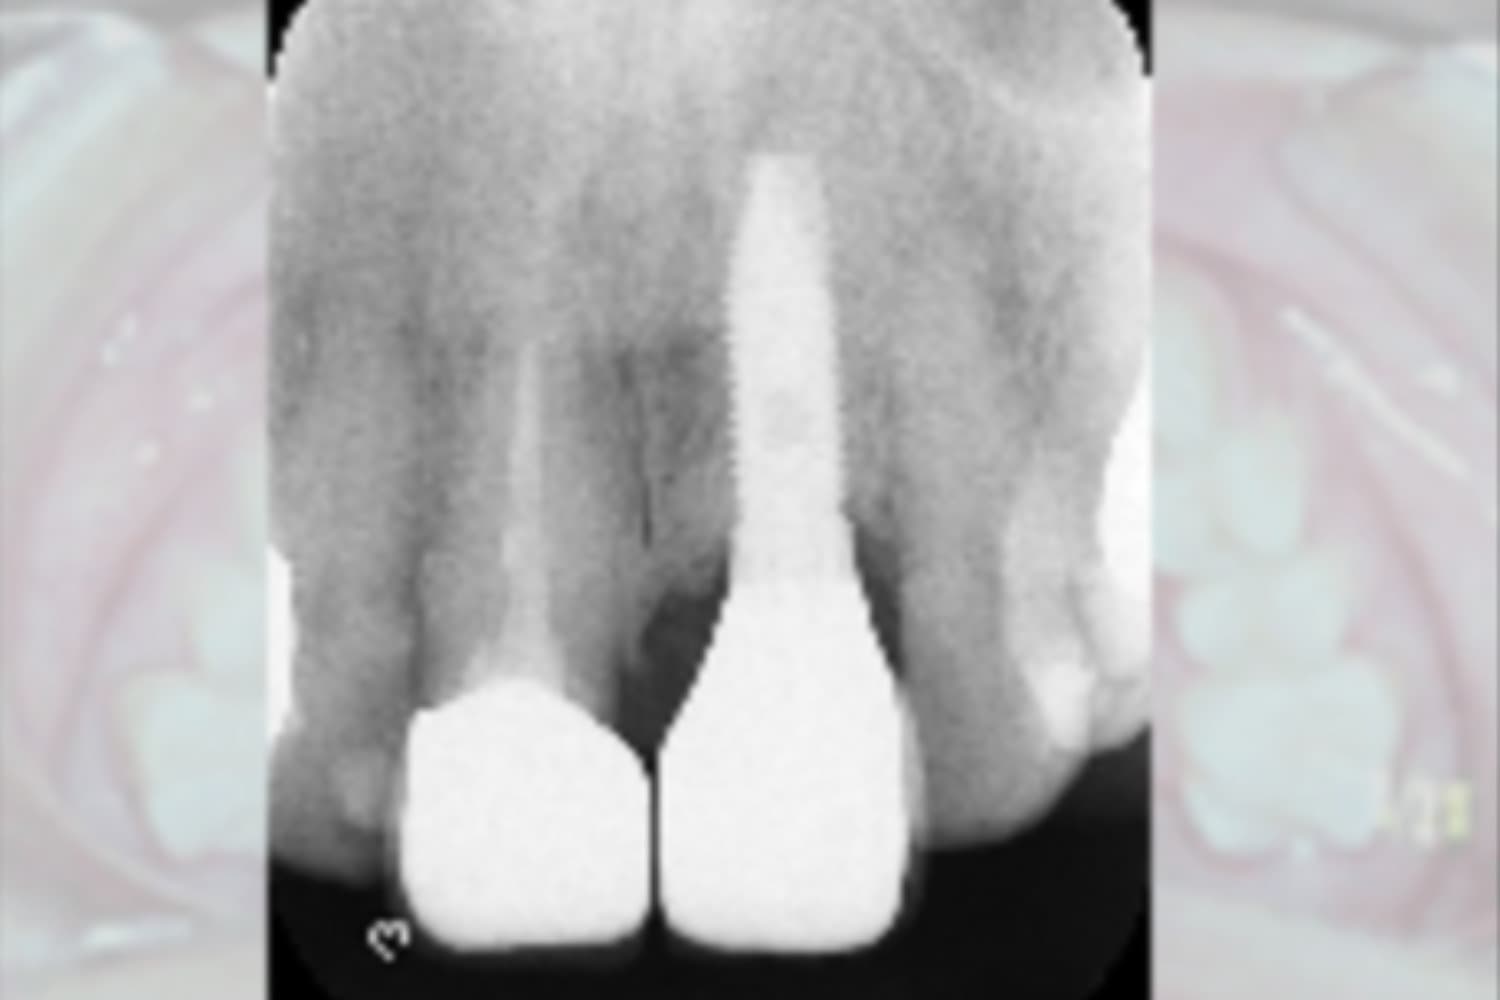

左上前歯のインプラント治療

Before

After

変色している歯は、根が割れているため抜歯し、インプラント治療を行なった。

主訴

左上前歯の変色

治療期間

5カ月

治療回数

10回

費用

533,500円

副作用・リスク

・抜歯と同時にインプラントを埋入するためで初期固定が得にくく、治癒期間が延長する可能性があります ・感染症のリスクがあります。